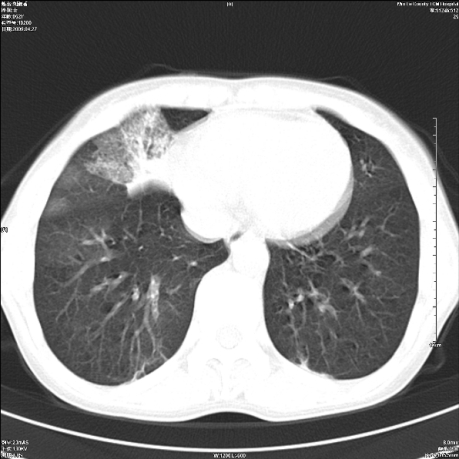

标题: CT19625:女52间断性喀血 [打印本页]

标题: CT19625:女52间断性喀血

考虑右肺中叶感染性病变并右肺中、下叶肺泡积血;建议抗炎、止血治疗后复查。

右肺中叶炎症;右肺中、下叶肺泡积血

右肺中叶支气管扩张并感染或咳血沉积,块右肺中下叶肺泡积血。

右肺中叶慢性炎症伴局部支扩并中下叶肺泡积血。

考虑右肺中叶感染性病变并右肺中、下叶肺泡积血。建议治疗后复查。